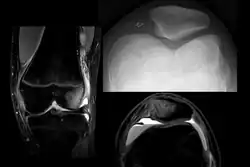

X-ray and MRI after luxation of the patella. There is a fragment and bone bruise at the medial surface of the patella and in the corresponding surface of the lateral condyle of the femur. The medial retinaculum of the patella is disrupted.

Displacement of the patella laterally out of its groove strains the medial stabilizing connective tissues, particularly the medial patellofemoral ligament (supporting 50–80% of the knee mechanisms in lateral patellar glide), which is torn usually at its femoral attachment.[3] Traumatic patellar dislocation may cause bleeding into the joint space, ligament and muscle attachment tearing, and fracture of the medial wing of the patella.[3] Fracture of the weight-bearing portion of the lateral femoral condyle occurs in 25% of traumatic patellar dislocations.[3] Surgical repair of the patellar stabilizing structures – the medial patellofemoral ligament and vastus medialis muscle – may be needed for athletes.[3]